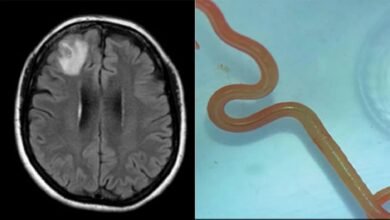

أول حالة لدى البشر.. أطباء يستخرجون من دماغ امرأة دودة حية طولها 8 سم توجد عادة بالثعابين

المصدر: سيدني أ.ف.ب أعلن أطباء أستراليون اليوم الثلاثاء أن دودة طفيلية دائرية تكون موجودة عادةً لدى الثعابين رُصدت للمرة الأولى…